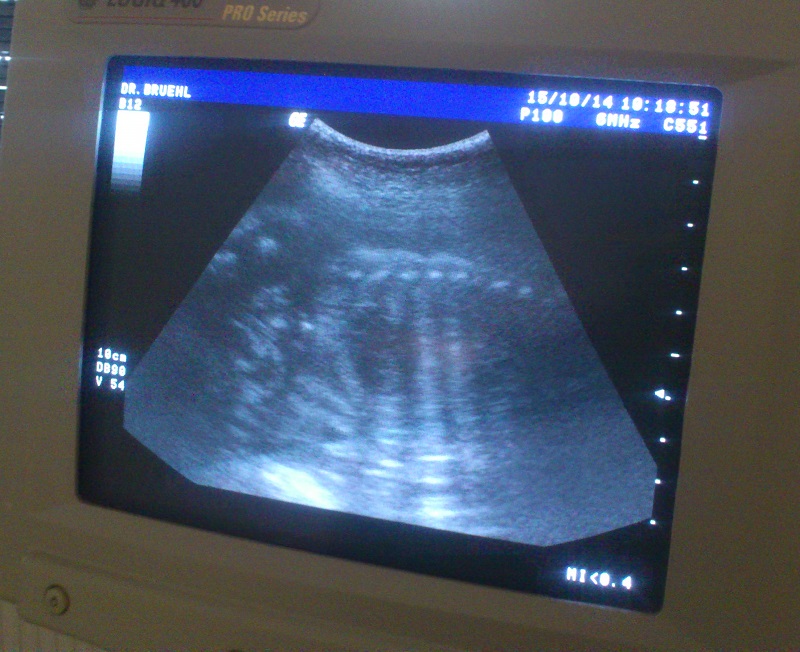

Hallo, ich hab's gesehen. Auf einem Bildschirm. Mein Baby. Groß und fit und vital. Ich hab die Wirbelsäule gesehen und die Rippen des Brustkorbs und wie das Herz schlägt. ![]() Und dann hat der Mann gesagt, dass es wohl nächste Woche zur Welt kommen wird. Ein Baby, mein Baby. Nur ob es ein Junge oder ein Mädchen wird, das konnte er nicht sagen. Aber jetzt habe ich vor lauter Aufregung wieder mal mit dem Ende der Geschichte angefangen und euch den Anfang unterschlagen. Also nochmal von vorn: Dass ich für mein Leben gerne Auto fahre, habe ich euch sicher schon mal erzählt. Jedenfalls war ich sofort Feuer und Flamme, als Herrchen mich eingeladen hat, einzusteigen. Und dieses Mal sind wir sogar recht weit gefahren. ![]() Es waren viele andere Hunde und Leute dort. Herrchen hat uns angemeldet und dann haben wir gewartet. Als wir drankamen, war da ein netter Mann, der hat mich untersucht. Dann sagte er: "Dann wollen wir mal reinschauen." Reinschauen? Der wird doch wohl nicht? Doch ich war beruhigt, als ich das Ding wiedererkannte, das er "Ultraschall" nannte. Und dann sagte er:"Da ist es ja - also schwanger ist sie auf jeden Fall." Als ob ich das nicht schon gewusst hätte. Und dann: "Ja, es ist tatsächlich nur eins." Wieso "nur" eins? Mir reicht das dicke. Und dann hab ich es auch gesehen. Auf einem Bildschirm Mein Baby. Groß und fit und vital. Ich hab die Wirbelsäule gesehen und die Rippen des Brustkorbs und wie das Herz schlägt. Und dann hat der Mann gesagt, dass es wohl nächste Woche zur Welt kommen wird. Ein Baby, mein Baby. Nur ob es ein Junge oder ein Mädchen wird, das konnte er nicht sagen. Und was Herrchen jetzt mit seinen 27 Namensvorschlägen macht, die alle mit G beginnen, weiß ich nicht. Ist mir aber auch egal. Für mich wird es eh nur "Baby" heißen. Das fängt zwar nicht mit G an, ist aber nicht mein Problem. Bis bald Eure Keeana |